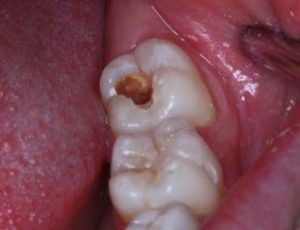

Commonly, decay starts on the chewing surface (occlusal surface) and has multiple stages prior to becoming “soft or sticky.” This progression commonly leads to more sensitivity in the tooth and provides a highway for the decay to approach the pulp. The decay progression through the enamel is based on several factors including but not limited to:

Next, the dentin layer is softer by nature and contains cells called odontoblasts. Proceeding through the dentin layer, the decay encroaches upon the pulp and this is the point that commonly patients go from needing a filling to needing a root canal. Some common signs and symptoms associated with decay encroaching on the pulp include sleepless nights, obvious signs of infection like swelling or redness and sensitivity to hot/cold lasting over 15-30 seconds.